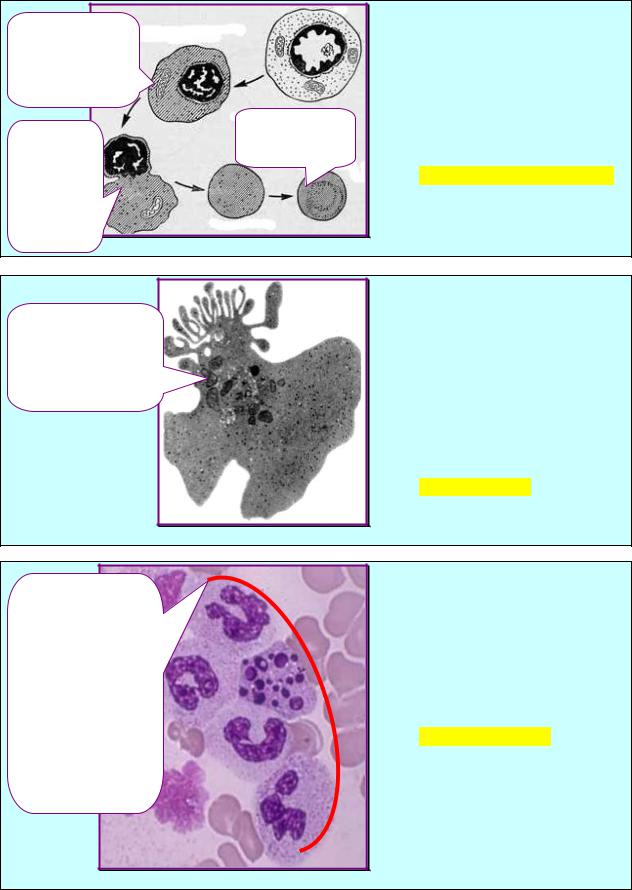

На схеме (рис.3.24) представлен |

путь |

развития |

клетки |

миелоидной |

ткани, |

обозначенной |

красной |

стрелкой. |

Рис. 3.24 |

Базофилы |

ЗАДАНИЕ 3.25 |

Лимфоцит |

В |

синусоидах |

красного |

костного |

мозга |

здорового |

человека |

выявили |

Эозинофилы |

рис.3.25. |

Моноцит |

Назовите данный класс клеток. |

Нейтрофилы |

Рис. 3.25 |

1.Стволовая клетка |

ЗАДАНИЕ 3.26 |

крови. |

У |

взрослого |

2.Полустволовая |

ткани |

клетка. |

3.КОЕ-ГМ. |

рис.3.26. |

Назовите |

данную |

4.КОЕ-М. |

5.Монобласт. |

группу клеток. |

6.Промоноцит. |

А. Клон. |

7.Моноцит. |

Б. Островок. |

В. Полный дифферон. |

Г. Неполный дифферон. |

Д. Фолликул. |

Рис. 3.26 |